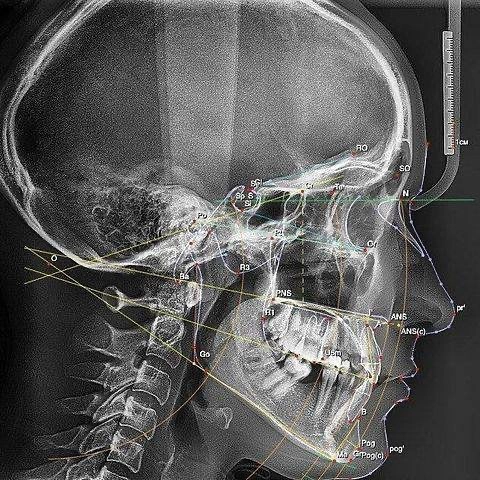

Телерентгенографія пряма та бокова проекції (ТРГ)

Телерентгенограма (ТРГ) – це один з підвидів рентгенівського знімка, який показує стан лицьової частини голови в прямій і бічній проекції. В результаті стоматолог зможе оцінити розташування щелепи, нахил зубів, стан лицьової тканини і т.д.

На відміну від внутрішньоротової діагностики, ТРГ дає детальну картину стану не тільки зубощелепної системи, а й кісток черепа. Активно використовується в ортодонтії, ортопедії і перед проведенням щелепно-лицьових оперативних втручань.